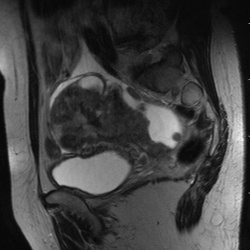

25.08.2011 - 12:21

Пациентка поступила в клинику с жалобами на подъём температуры, боли в левой подвздошной области. . Менопауза 6 лет. Варианты? (Ответ знаю). :-)